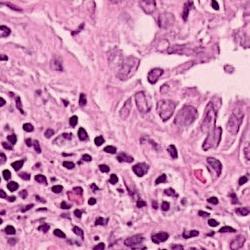

Histopathology plays a vital role in cancer diagnosis, prognosis, and treatment decisions. Histopathology slides are created from formalin-fixed paraffin-embedded (FFPE) tissue containing both tumor and surrounding normal tissue. These slides are then stained with agents such as hematoxylin and eosin (H&E) and immunohistochemical stains that permit the pathologist to ascertain important features. For instance, pathologists routinely determine the type of cancer, stage of cancer, cancer’s grade, presence of infiltrating immune cells, and potential treatment options based on histopathology slides. Whole slide imaging allows the pathologist to view the slides digitally as opposed to what was traditionally viewed under a microscope. With improvements in computational power and image analysis algorithms, computational methods [1, 2, 3, 4] have been developed for the quantitative and objective analyses of histopathology images, which can reduce the intensive labor and improve the efficiency for pathologists compared with manual examinations. Nuclei segmentation is a critical step in the automatic analysis of histopathology images, because the nuclear features such as average size, density and nucleus-to-cytoplasm ratio are related to the clinical diagnosis and management of cancer. Besides, clinical sequencing of cancer specimens is becoming routine and nuclei segmentation algorithms will play a key role in the proper interpretation of these sequencing results.

To validate the proposed framework, we conduct experiments on two datasets of H&E stained histopathology images.

5.1.1 Lung Cancer (LC) dataset

We generated this dataset by extracting 40 images of size from 8 lung adenocarcinoma or lung squamous cell carcinoma cases, i.e., H&E stained WSIs with 20x magnification. They are split into the training, validation and test sets, consisting of 24, 8 and 8 images, respectively. 24401 nuclei are annotated with masks.

5.1.2 Multi-Organ (MO) dataset

It is a public dataset released by Kumar et al. [10], and consists of 30 images of size which are taken from multiple hospitals including a diversity of nuclear appearances from seven organs [10]. The variability in this dataset is large because of the heterogeneity between organs and cancer types. There are 12, 4 and 14 images in training, validation and test sets.